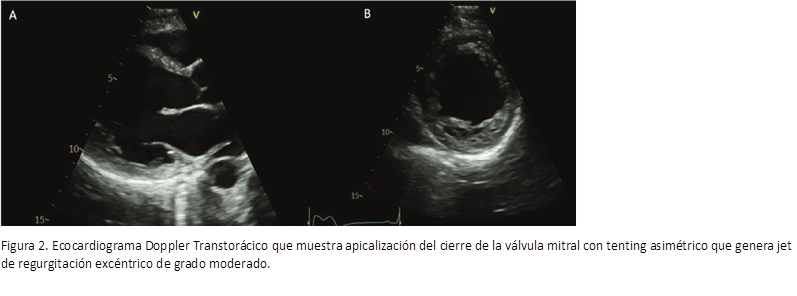

Los controles con ecocardiograma evidenciaban VI dilatado. Disquinesia septal e hipocontractilidad global.

FEVI 40-41%, AI moderadamente dilatada. Insuficiencia mitral leve. Insuficiencia tricuspídea leve con presión sistólica de la arteria pulmonar de 24 mmHg. Sin otros cambios con respecto al ecocardiograma previo al embarazo (figuras 1 y 2).

Figura 1. Ecocardiograma transtorácico. A-B: enfoque paraesternal eje largo y corto respectivamente que evidencia un ventrículo izquierdo moderadamente dilatado con pérdida de su geometría (remodelado esférico).